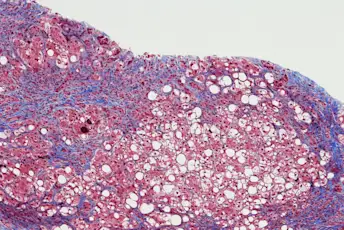

肝损伤是否可逆?

肝脏是一个神奇的器官,具有独特的愈合能力,所以治愈丙肝可能会让肝脏逆转损伤,并随着时间的推移自我愈合。